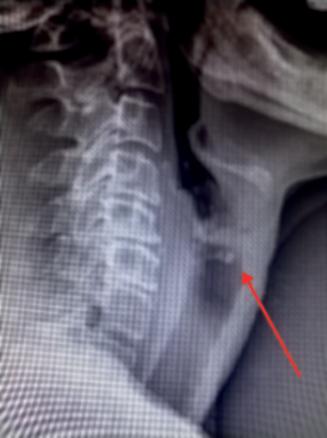

La radio standard, prescrite en urgence, met en évidence un corps étranger (CE) situé au niveau du carrefour aéro-digestif (fig. 1). Une ablation par laryngoscopie est préconisée.